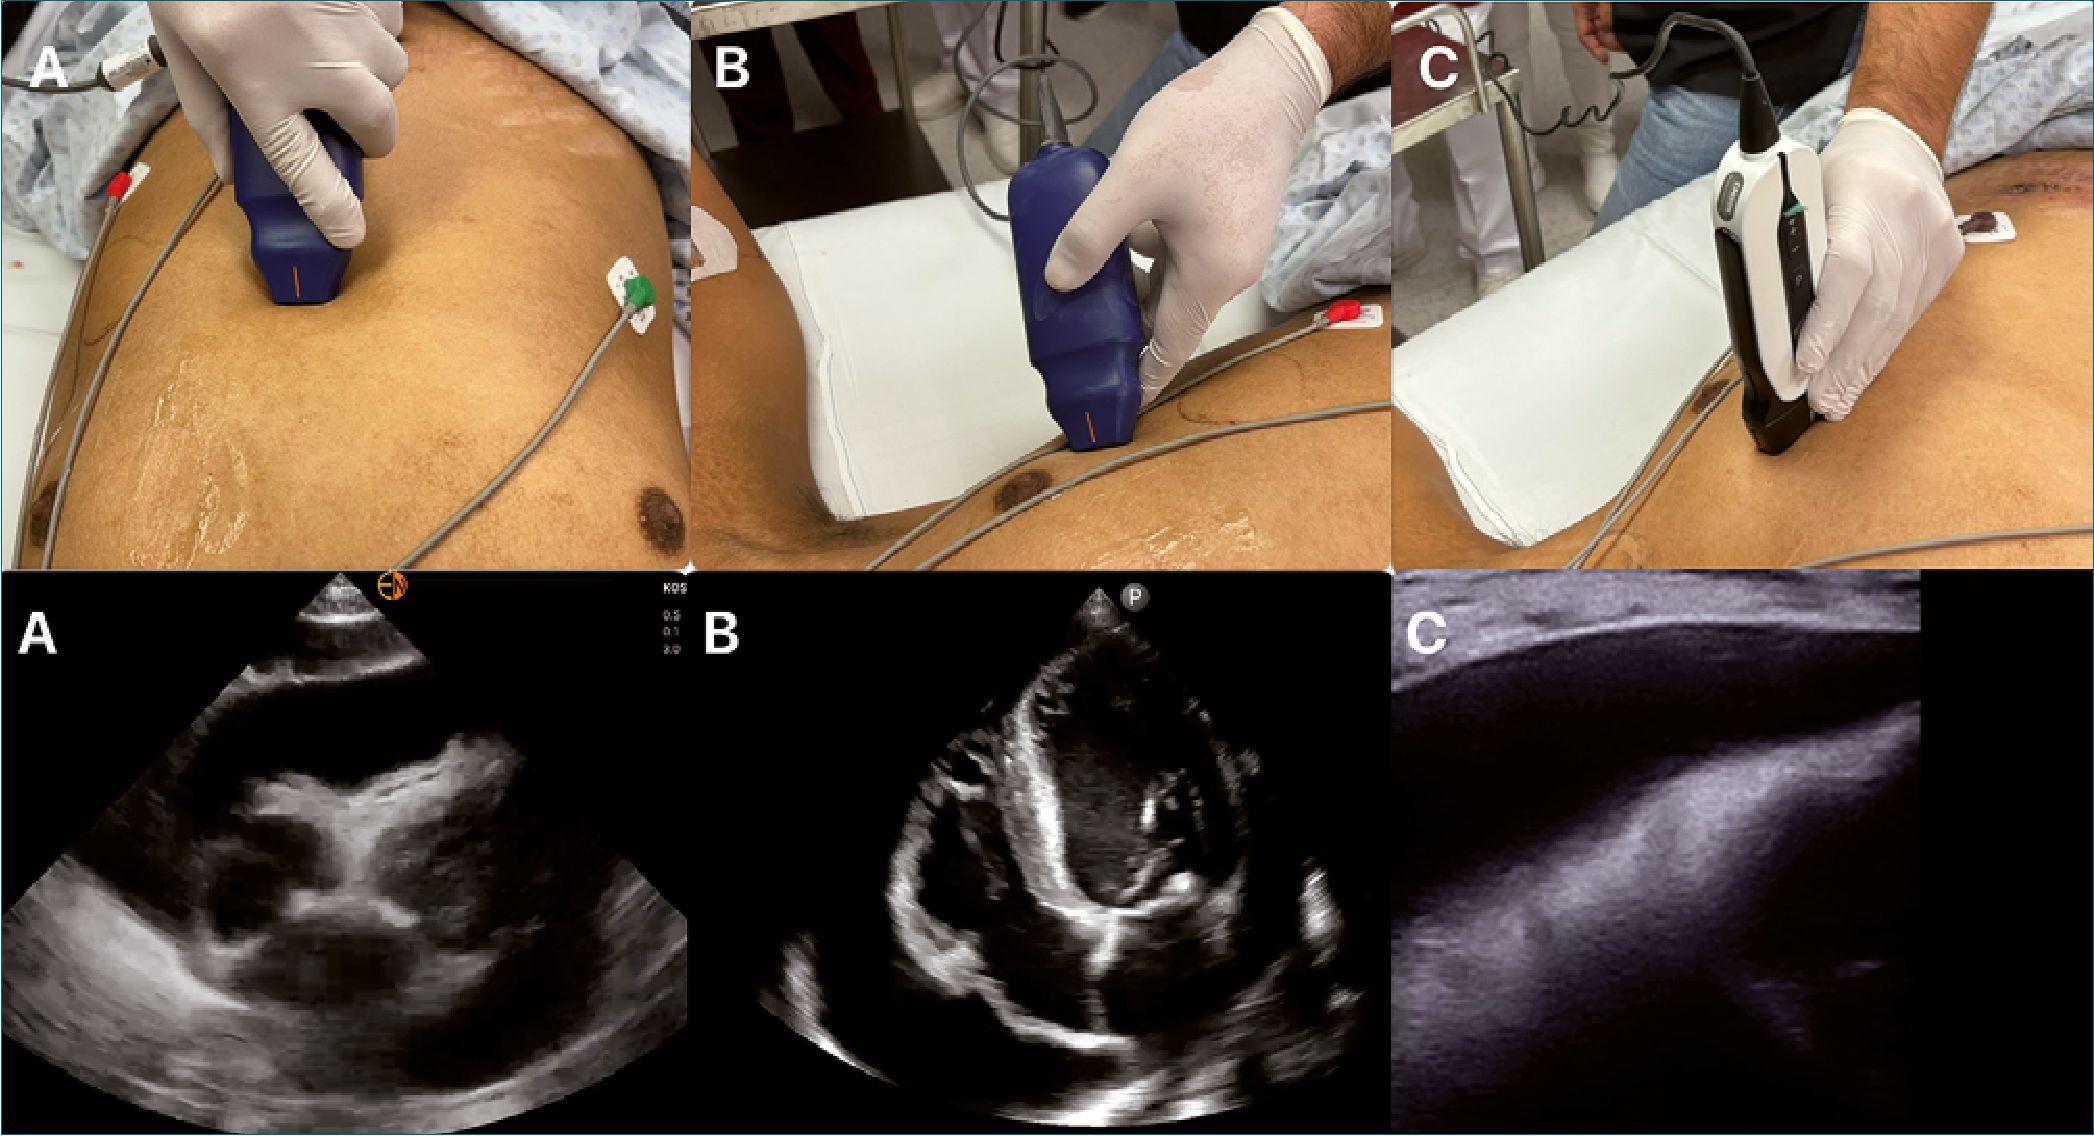

Existen 3 abordajes descritos en la literatura (Figura 3)

Figura 3. Ventanas para pericardiocentesis ecoguiada. A: subxifoidea; B: Apical; C: Intercostal o paraesternal.